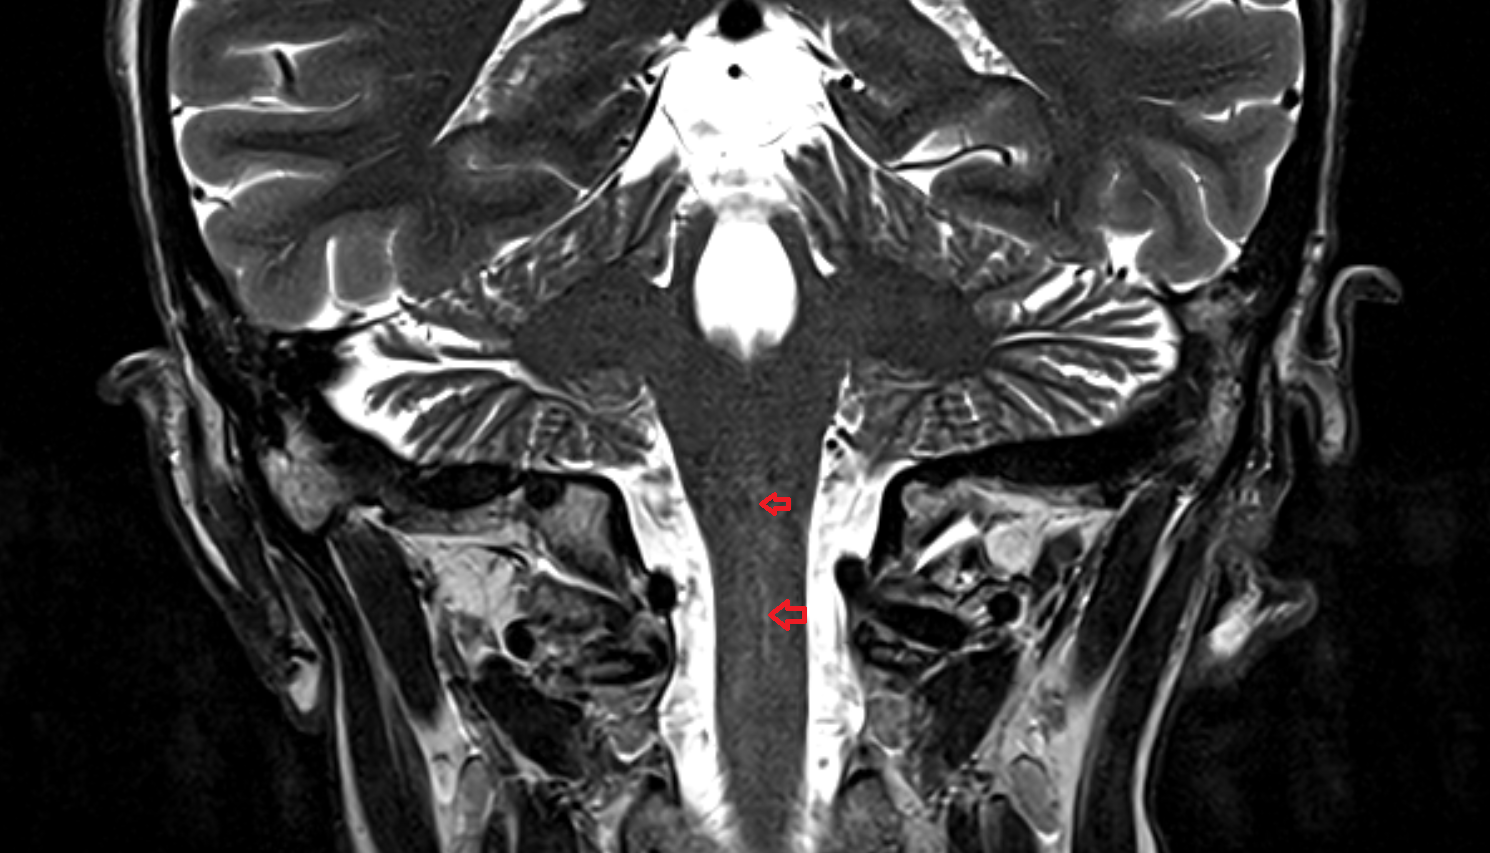

- Upper cervical spinal cord

- Spinal cord

- subarachnoid space of spinal cord